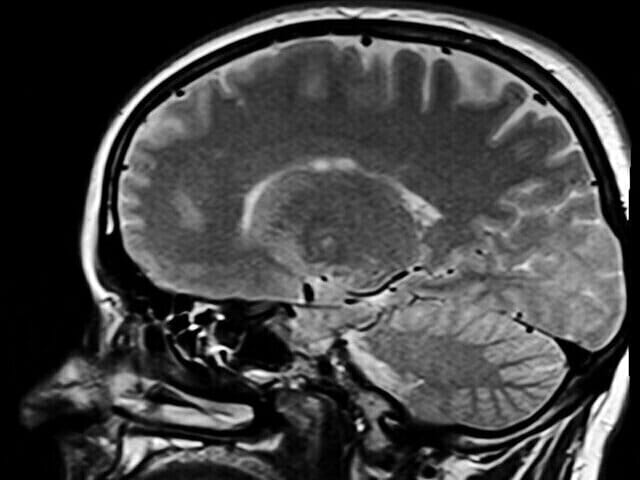

• CT scans and other tests